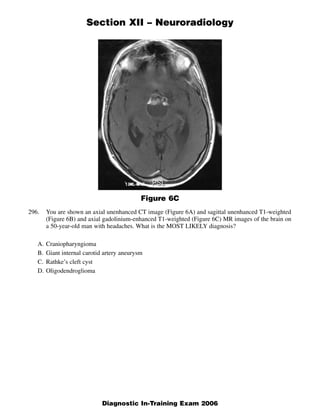

The document discusses several radiology cases involving the brain and spine. Question 291 presents CT scans of a woman with headaches and asks for the most likely diagnosis of a fat-containing extraconal orbital mass. Question 292 shows MR images of a woman with extremity weakness and asks for the most likely diagnosis of multiple brain and spine lesions. Question 293 presents MR images of a man with back pain and asks for the diagnosis of a posterior spinal mass seen on the images.